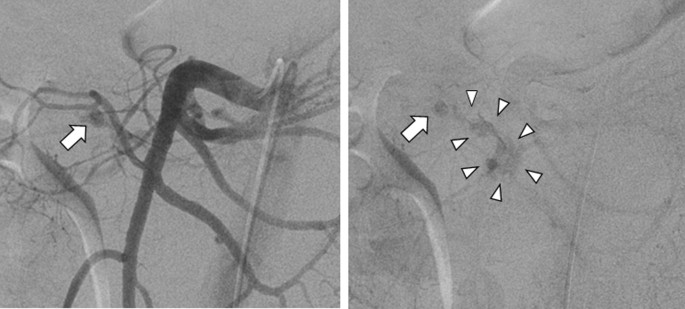

A 47-year-old Japanese man, stabbed in the back with a knife, was transferred to our emergency room. He presented with a stab-wound in his left back, and slight tenderness in his abdomen; although his hemodynamic state was unstable, it was improved by a bolus infusion. Upon blood examination, most laboratory parameters were normal, including hemoglobin and coagulation; both serum amylase and lipase levels were within normal ranges (61 U/L and 9 U/L, respectively). Contrast-enhanced computed tomography (CECT) showed extravasation of the contrast medium around the pancreatic head, as well as hematomas behind the pancreas and in the left psoas muscle (Fig. 1); no other visceral or major vascular injuries were presented. We performed abdominal arterial angiography and extravasation of the contrast medium through the inferior pancreatoduodenal artery (IPDA), revealing a pseudo aneurysm in the IPDA branch (Fig. 2). Coil embolization of the IPDA was therefore performed, and the hemodynamic state was stabilized.